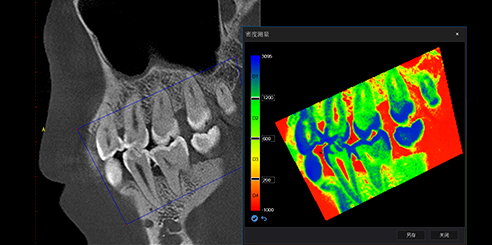

AI + Low-Dose Dental CBCT Technology

- The integrated AI image processor enhances CT quality while reducing radiation exposure.

Consequently, each 3D scan provides superior clarity at a lower dose, ensuring patient safety.

T-MAR Metal Artifact Reduction in LargeV Dental CBCT

With the new T-MAR module, the system automatically removes metal artifacts and corrects image distortions intelligently.

Hence, the final images remain clear, accurate, and clinically reliable.